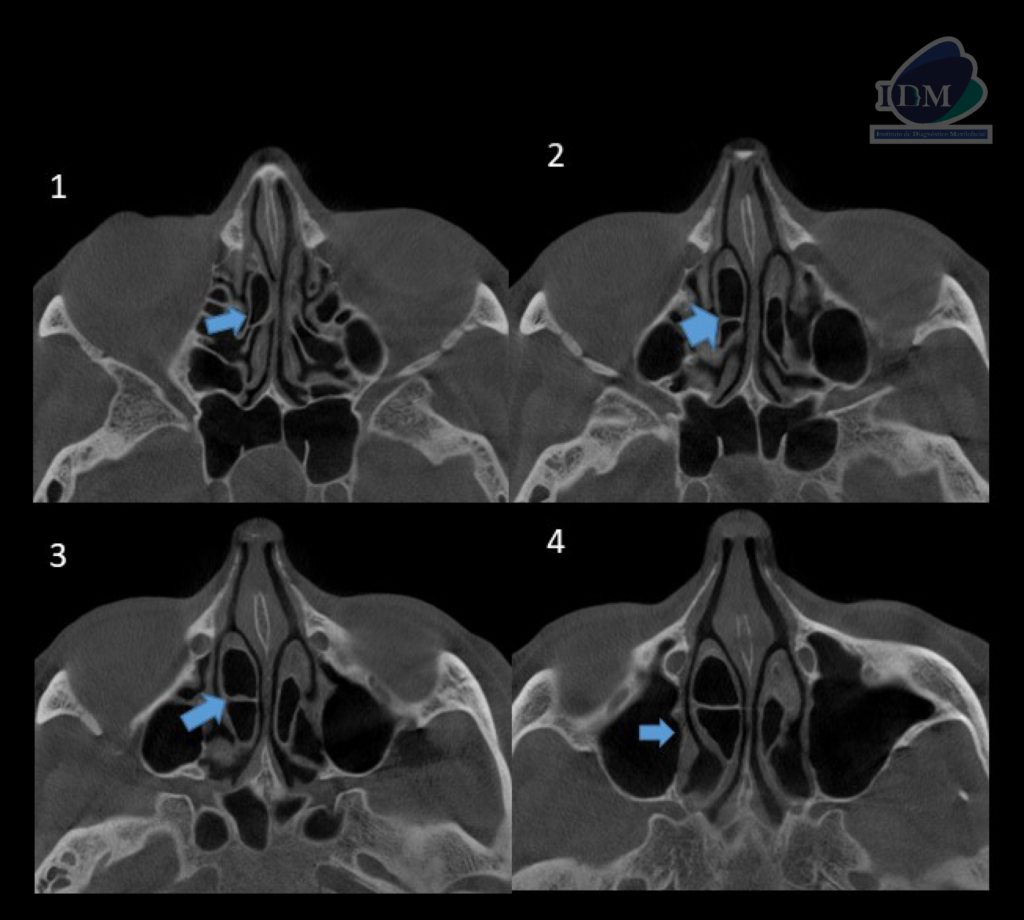

A la evaluación de la tomografía computarizada de macizo facial en los cortes axiales, coronales y sagitales se observa la neumatización de los cornetes medios a predominio del lado derecho que se presenta como una imagen hipodensa de forma irregular y limites definidos, asimismo se evidencia la presencia de un septo intrasinusal vertical a nivel de la porción media del cornete medio del lado derecho y la levodesviación del tabique nasal, signos imagenológicos compatible con concha bullosa.

CORTES AXIALES